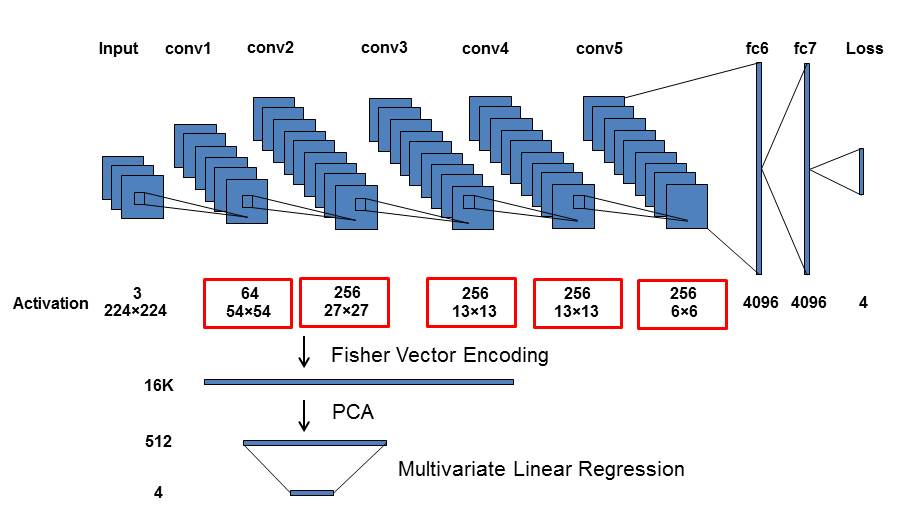

In this section, we propose three variations of multi-label deep convolutional neural network classification or regression models to address the multi-label ILD detection challenge. First, an end-to-end CNN network is trained using a multi-label image classification loss layer. Second, we outline a CNN network that uses a continuously-valued regression formulation, estimating either the actual pixel numbers occupied per ILD class per CT image or the binary [0,1] occurring status. Third, the convolutional image activation feature maps at different network depths are spatially aggregated and encoded through the orderless Fisher vector (FV) encoder [21]. This encoding scheme removes the spatial configurations/layouts of convolutional activations and turns them into location-invariant feature representations. This type of CNN is referred to as FV-CNN [19]. The formed orderless features are then trained with a multivariate linear regressor (Mvregress() function in Matlab) to regress the ILD pixel numbers or binary labels.

3.3 Unordered Pooling via Fisher Vector Encoding for Multivariate Linear Regression

Both classification and regression CNN models (Sec. 3.1 and 3.2) can be seen as performing the spatially order-sensitive feature pooling through their use of fully-connected CNN layers. In this section, we investigate whether the spatial information captured inside CNN activation maps is beneficial for a task-specific image recognition problem. The typical representation of deep hierarchical CNN features inherits the gross image-activation spatial layouts. We are motivated by the observation that ILD patterns could happen anywhere inside the lung region, implying that the spatial layout may not be a strongly-correlated factor to ILD recognition. CNNs are designed to learn special feature layouts from the limited annotated ILD imaging data, which may be subject to over-fitting more easily. In our implementation, CNN activations are extracted from the convolutional layers at various depths of the CNN network and compiled using the Fisher vector (FV) feature encoding scheme [21, 19], allowing us to achieve a location-invariant deep texture description. ILD class labels can then be predicted via the simple multivariate linear regression.

The output of each -th convolutional layer is a 3D descriptor or matrix , where and are the width and height of the spatial reception field and is the number of feature channels. In this sense, the specific deep feature activation map is represented by feature vectors and each feature vector is dimension. We invoke the FV encoding to remove the spatial configurations of total vectors (denoted as the set ) for each activation map. Following [21], each feature descriptor is soft-quantized using a Gaussian mixture model. The first- and second-order differences between any descriptor and each of the Gaussian cluster mean vectors are accumulated into a -dimensional image representation:

| (4) |

FV feature encoding produces a very high dimensionality of from the deep feature activations of for each image (e.g., and ). For computational and memory efficiency, we adopt principal component analysis (PCA) to project the vectors to a lower-dimensional parameter subspace. Using their ground-truth ILD label vectors , the multivariate linear regression Mvregress() function in Matlab is called to predict the presence or non-presence of ILDs from the low-dimensional projected image feature vectors .

4.5 Unordered Pooling via Fisher Vector Encoding

When constructing the FV-encoded features, , the local convolutional image descriptors are pooled into Gaussian components, producing a dimensionality as high as 16K [21]. We further reduce the FV features to dimensions using PCA. The performance is empirically found to be insensitive to the number of Gaussian kernels and the dimensions after PCA. We compare the ILD classification performance with FV encoding, on the features pooled from different CNN layers, using area-under-the-curve (AUC) values (in Table 5) and F-scores (in Table 6), respectively.